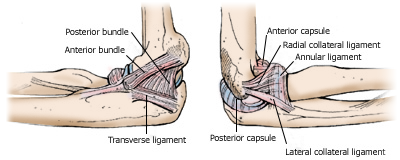

Elbow anatomy

The ligaments of the elbow on the inner side (left) and outer side of the joint (right).